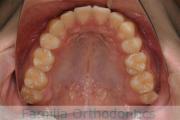

横顔が気になるとのことで来院されました。叢生(でこぼこ、凹凸、ガタガタ)を伴う上下顎前突(口元が出ていること)を呈しているため、上下左右から小臼歯を抜歯して歯科矯正用アンカースクリューとマルチブラケットにより2年弱の治療を行いました。

上顎

下顎